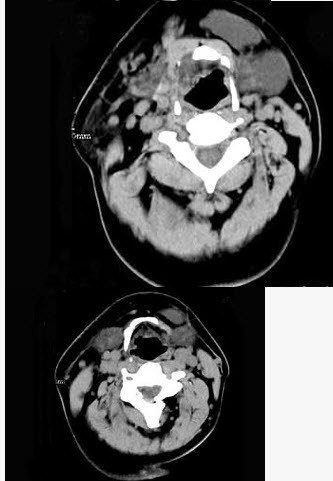

男,32岁,左侧下颌部肿块,CT如图所示,最可能的诊断是()。

A、造釉细胞瘤

B、颌骨囊肿

C、鳃裂囊肿

D、颈部淋巴管瘤

E、舌下腺囊肿

正确答案:

E